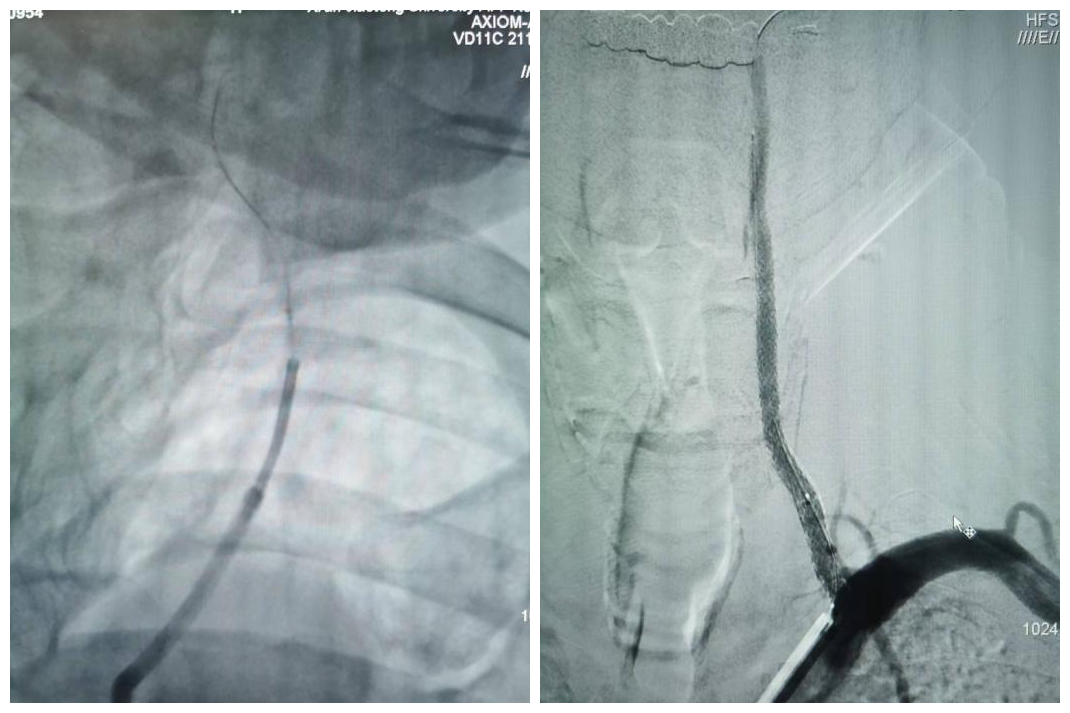

最终,在患者入院第4天,张桂莲教授带领的介入团队选择局麻条件下为患者成功实施了神经介入领域的高难度手术—左侧无残端椎动脉长节段慢性闭塞再通术。因术前清晰的影像显影及准确的体外定位标记,左侧优势椎动脉顺利开通,手术耗时仅仅约90分钟。术中及术后患者配合良好,无任何不适,术后在介入准备室,张桂莲教授向患者女儿详细告知手术过程及患者目前状况,患者女儿喜极而泣,多次向介入团队表示感谢。

出院前复查头颈一体化超声提示左侧椎动脉支架位置良好,血流通畅,颅内血流速度及频谱未见明显异常。充分向患者及家属告知出院注意事项及复查时间后,目前该患者已顺利出院。